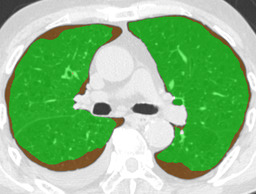

Recall, precision, and dice coefficient (a.k.a F-measure) were used for the evaluation. For the sake of the evaluation, continuous softmax outputs were converted into discrete class labels by selecting the classes that gave the maximum probability. Table 2 shows the evaluated metrics for each method. By paired t-tests, statistically significant differences were confirmed between the proposed method (λ=0.1𝜆0.1\lambda=0.1) and other methods in dice coefficients. As shown in Table 2, utilizing weakly annotated pixels increased precision and λ=0.1𝜆0.1\lambda=0.1 was the optimal value that balances recall and precision in this experiment. Evaluated dice coefficients for the proposed method (λ=0.1𝜆0.1\lambda=0.1) are shown in Figure 2. As shown in Figure 2, even though the proposed method improved the segmentation accuracy, segmentation accuracy varies between slices. Figure 3 shows the confusion matrix of the pixel-wise classification result. In Figure 3, Lweaksubscript𝐿𝑤𝑒𝑎𝑘L_{weak} pixels misclassified as corresponding Lstrongsubscript𝐿𝑠𝑡𝑟𝑜𝑛𝑔L_{strong} (e.g. pixels of lCON¯subscript𝑙¯𝐶𝑂𝑁l_{\overline{CON}} classified as lCONsubscript𝑙𝐶𝑂𝑁l_{CON}) are represented as “Others”. As shown in Figure 3, DLD class combinations with similar texture patterns such as HCM and EMP were misclassified into each other. Figure 4 shows the average result for each DLD class and tested method.

Ground truth Supervised only Proposed (λ=0.1𝜆0.1\lambda=0.1) Proposed (λ=1𝜆1\lambda=1)

EMP \blacksquare

Refer to caption Refer to caption Refer to caption Refer to caption

0.793 0.847 0.815

Figure 4: Average results and dice coefficients for each DLD pattern. Automated segmentation results are superimposed with colors. For each DLD pattern, the slice that gave the median dice coefficient for the proposed method with λ=0.1𝜆0.1\lambda=0.1 was chosen to represent the average result. Note that although CNN performed multi-class segmentation, only one DLD pattern per slice was taken into account for the evaluation.